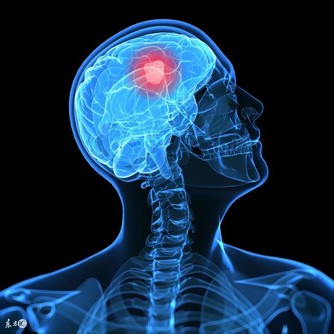

部分引起慢性便秘的病因危險性很大,如肛門損傷、腸梗阻、腸嵌塞或潰瘍、腸道惡性腫瘤等,此時最好及時到專科門診就診,以免延誤疾病診治。